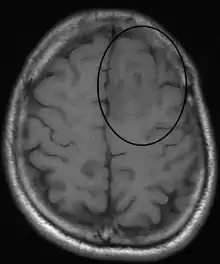

في خمسين إلى ثمانين بالمائة من الحالات، يكون العرض الأول لورم الدبقيات القليلة التغصن هو بداية نشاط النوبات. تحدث النوبات بشكل رئيسي في الفص الجبهي، يليه الفص الصدغي.[4]حوالي 60٪ من الأشخاص يعانون من نوبات قبل التشخيص.[3]يعتبر الصداع مترافقاً مع زيادة الضغط داخل القحف أحد الأعراض الشائعة أيضاً لورم الدبقيات القليلة التغصُّن. اعتمادًا على موقع الورم، يمكن أن يحدث أي عجز عصبي، بما في ذلك فقدان البصر وضعف الحركة والتدهور المعرفي. يعتبر التصوير المقطعي المحوسب (CT) أو التصوير بالرنين المغناطيسي (MRI) ضروري لتوصيف تشريح هذا الورم (الحجم والموقع والتغاير/التجانس). ومع ذلك، يعتمد التشخيص النهائي لهذا الورم، مثل معظم الأورام، على الفحص النسيجي المرضي (فحص الخزعة).

- اختبارات التصوير: يمكن أن تساعد اختبارات التصوير في تحديد موقع وحجم ورم الدماغ. غالبًا ما يُستخدم التصوير بالرنين المغناطيسي لتشخيص أورام الدماغ، ويمكن استخدامه جنبًا إلى جنب مع التصوير بالرنين المغناطيسي المتخصص، مثل التصوير بالرنين المغناطيسي الوظيفي ومطيافية الرنين المغناطيسي. قد تشمل اختبارات التصوير الأخرى التصوير المقطعي المحوسب (الأشعة السينية) وانبعاث البوزيترون (PET). يمكن استخدام هذا التصوير لمعرفة ما إذا كان هناك ورم في المخ أم لا؛ يمكن أن يكشف أيضًا ما إذا كانت هناك تكلسات في الورم، لأن العديد من الأورام الدبقية القليلة التغصن لديها بعض التكلسات. يستخدم التصوير بالرنين المغناطيسي مجالًا مغناطيسيًا قويًا وموجات الراديو لإنشاء صور تفصيلية تكشف عن موقع الورم وأجزاء الدماغ المشاركة قبل الجراحة. في بعض الأحيان يتم إجراء التصوير بالرنين المغناطيسي مع تحسين التباين؛ يعني "التباين" حقن صبغة خاصة في الأوعية الدموية الفردية للكشف عن الأورام. لا تحتاج اختبارات التصوير لأجزاء أخرى من الجسم عادةً لأن الأورام الدبقية قليلة التغصُّن لا تنتشر خارج الجهاز العصبي المركزي.[10]